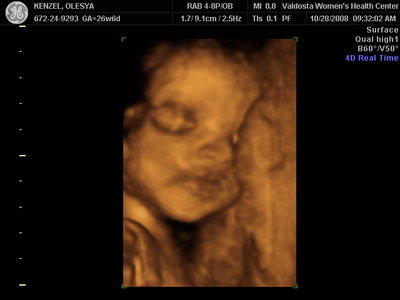

Еще одна Джианнка:

Вложения: |

KENZEL,OLESYA_5.JPG [ 60.02 КБ | Просмотров: 1236 ]

Катюш, какой прикольный бутузик ! Олесь, после фотки средней - точно прям похожи!